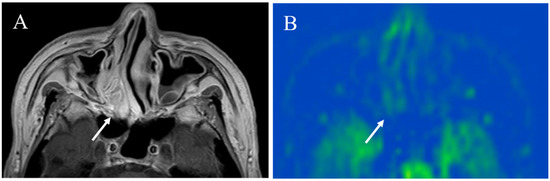

5.1.1. Inflammatory Lesions: Sialadenitis and Dacryoadenitis

- Takahashi, H.; Yamashita, H.; Morooka, M.; Kubota, K.; Takahashi, Y.; Kaneko, H.; Kano, T.; Mimori, A. The utility of FDG-PET/CT and other imaging techniques in the evaluation of IgG4-related disease. Jt. Bone Spine 2014, 81, 331–336. [Google Scholar] [CrossRef] [PubMed]